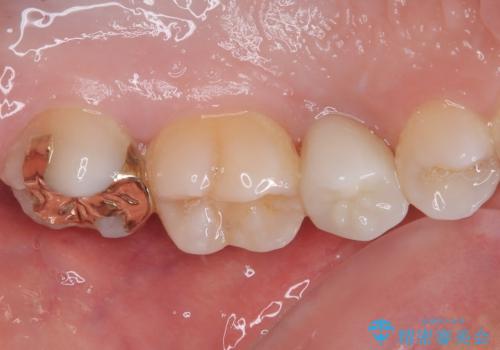

噛み合わせが強く、以前にも当院で右上でゴールドインレーにより治療をされていたのでゴールドインレーにて治療しました。

拡大鏡視野下で、虫歯の除去を行い、ゴールドインレーに適した形に整えました。

ゴールドインレー(PGAインレー)はセラミックインレーと比べ、歯の切削量が少なく、適合性が著しくいいことが特徴です。上顎の奥歯は見えないので機能面でゴールドインレー、ゴールドクラウンはおすすめです。